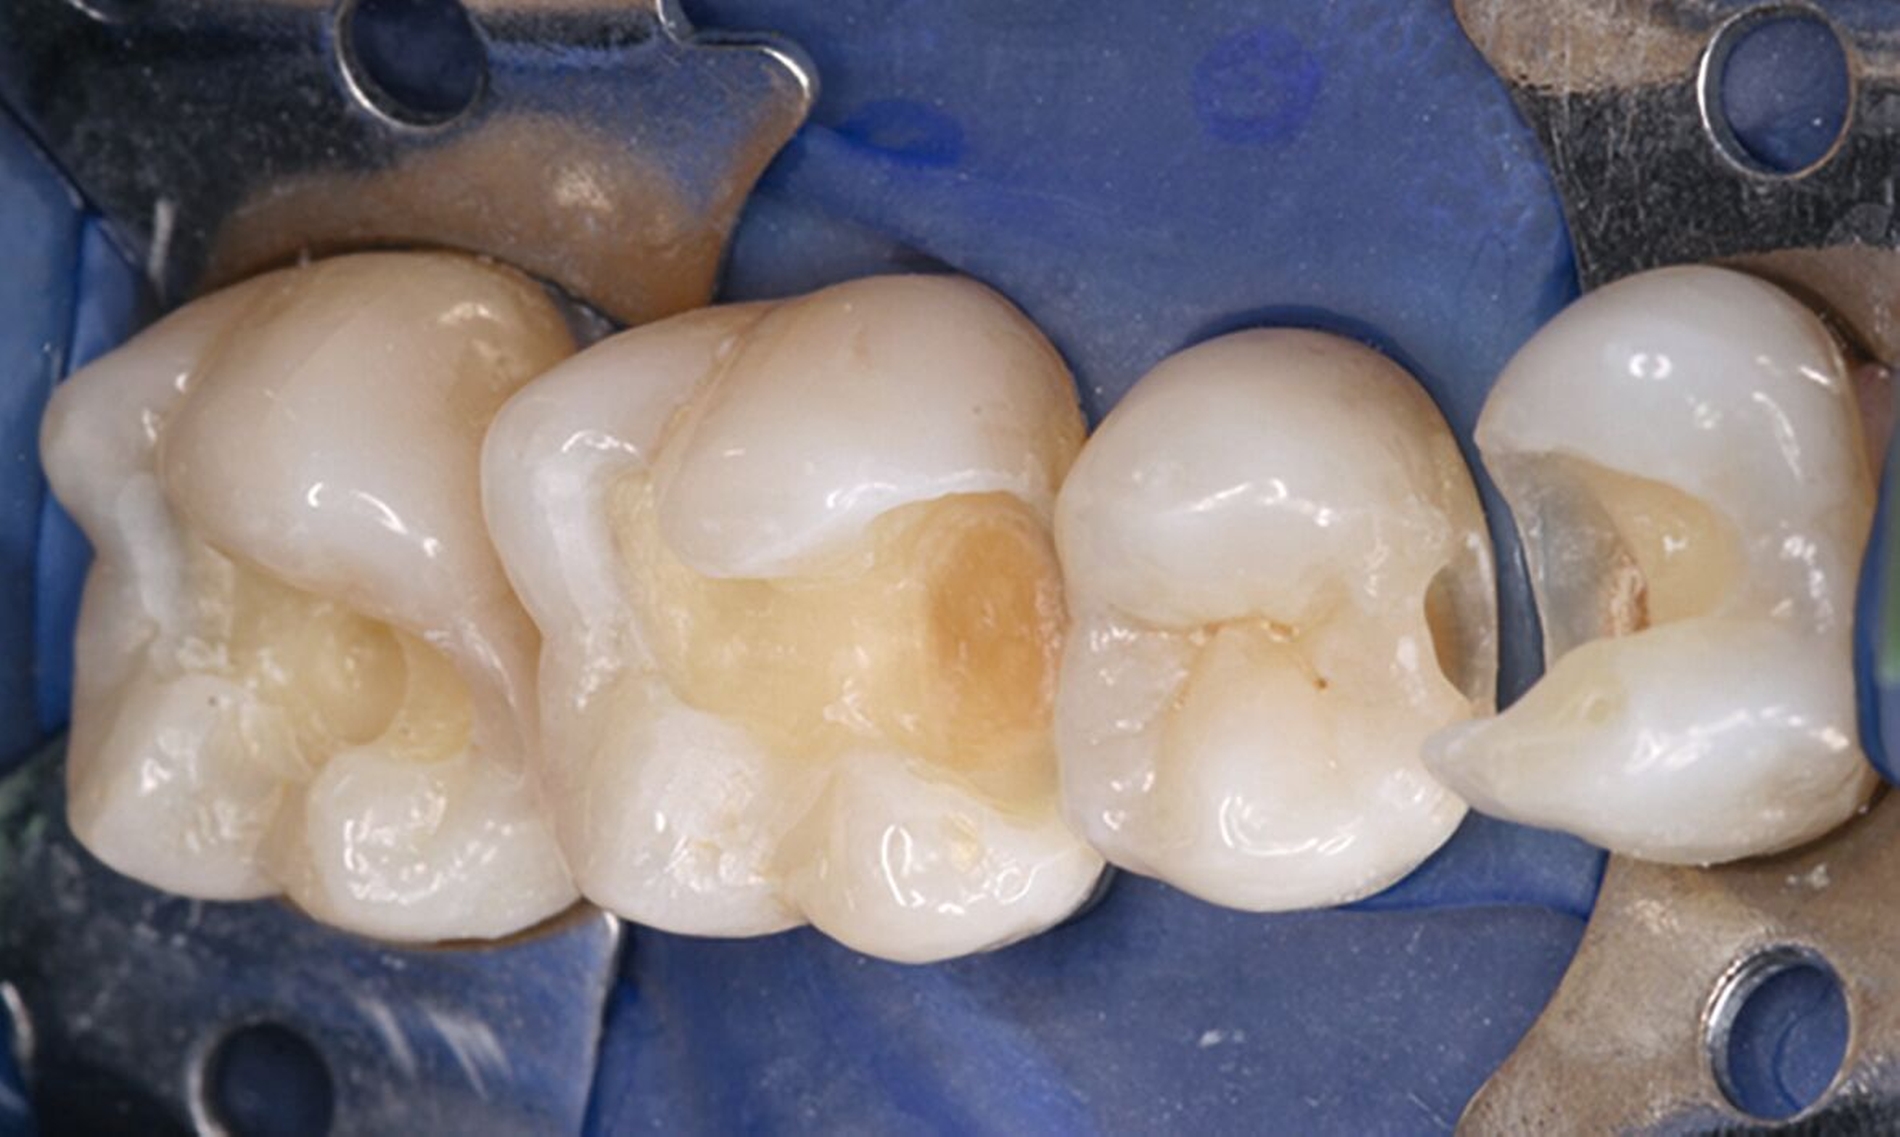

Eine besondere Situation stellt die Caries profunda dar. Hier gibt es hinreichend Evidenz, dass unterhalb einer Restdentindicke von 300 μm zum einen die Gefahr besteht, dass kurzkettige Monomere das Dentin durchdringen und Biomineralisationsprozesse der Odontoblasten stören können [Galler et al., 2011; Schmalz et al., 2001]. Praktisch viel wichtiger ist jedoch ein rein geometrisches Problem: Bondet man eine Kompositrestauration im Dentin so nahe an der Pulpa, bilden sich neben der für die Dentinhaftung verantwortlichen Hybridschicht auch Harzzotten (Resin Tags), die bis zu 300 μm in das Dentin eindringen (Abbildung 2). Das würde bedeuten, dass sich die Tags praktisch am Eingang der Pulpa befinden, was weder klinisch noch anatomisch sinnvoll erscheint. Gleiches gilt für pulpanahe Bereiche bei Kronenfrakturen. Insbesondere bei Kindern sind die Dentintubuli noch weit offen und das Dentin ist an diesen Stellen hoch permeabel [Krastl et al., 2021].

Für solche tiefen Areale existieren zwei unterschiedliche Lösungsansätze: Entweder man exkaviert einfach weniger aggressiv [Schwendicke et al., 2013] oder man appliziert ausschließlich in diesen Bereichen kleine Mengen klassischer „Cp-Medikamente“ oder Kalziumsilikatzemente [Schmidt et al., 2020] im Sinne einer kleinen Unterfüllung zur Blockade der „Tags“ [European Society of Endodontology, 2019]. Der weniger tief exkavierte Rest der Kavität wird aber auch hier vollständig mit einem Adhäsivsystem versiegelt und nicht mit einer konventionellen Zementunterfüllung [Arandi et al., 2020; European Society of Endodontology, 2019]. Eine korrekte Indikationsstellung für die Applikation eines Cp-Materials ist jedoch wichtig, da diese Materialien die Gesamthaftung in der restlichen Kavität reduzieren können [Frankenberger et al., 2021]. Die adhäsive Dentinversiegelung stellt heute den wirksamsten Schutz des Pulpa-Dentin-Komplexes dar (Abbildungen 3 und 4) [Arandi et al., 2020]. Das Risiko, dass die Pulpa dadurch einen irreversiblen Schaden erleidet, ist äußerst gering und minimal im Vergleich zum Schädigungspotenzial eines Diamantschleifers, der bei Amalgam und Gold oftmals „im Gesunden“ statt rein minimalinvasiv verwendet werden musste [Olmez et al., 1995; Schweikl et al., 2017].